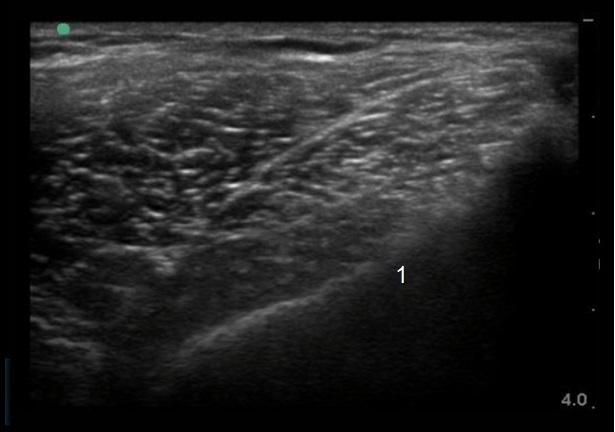

Bild: Ilium der lateralen Hüfte 1

Ilium